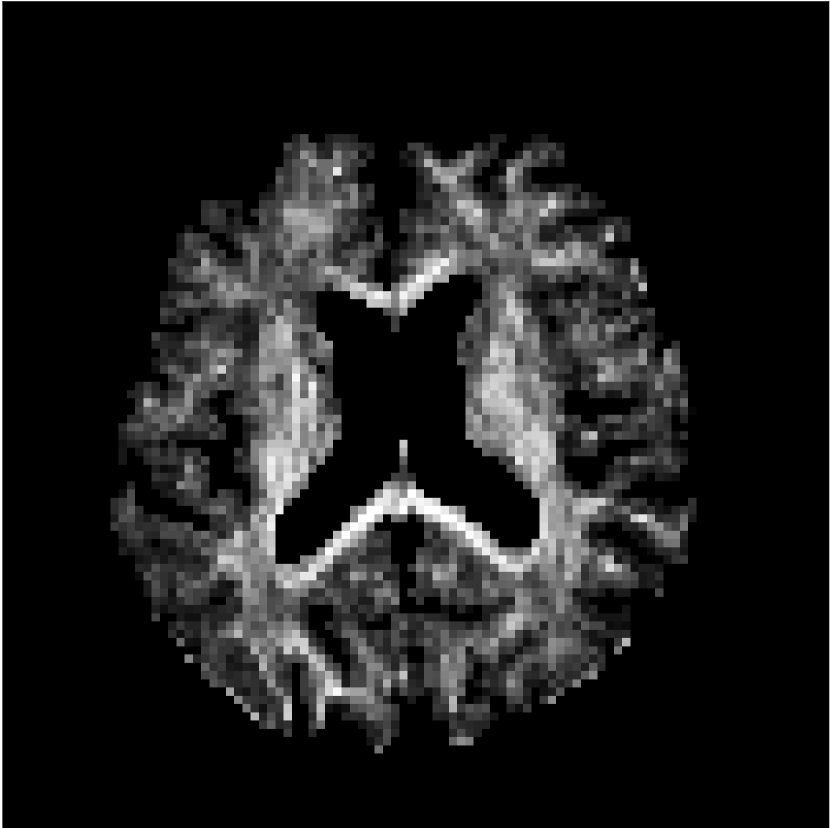

Figure 10 compares mean diffusivity maps across various partial Fourier factors between the CCNN and state-of-the-art methods.

No PF

7/8 PF

6/8 PF

5/8 PF

SoA

MD, m2/ms

CCNN

The methods perform similarly without partial Fourier acceleration, but as partial Fourier acceleration increases, the image is continually degraded in the SoA method, with "black voxels" appearing around the lateral ventricles. The CCNN method mitigates the appearance of these artifacts in the parameter maps.